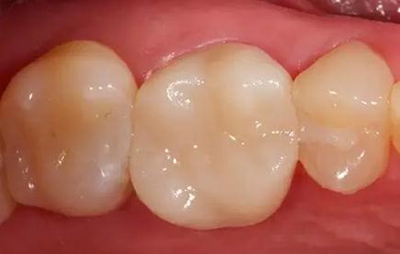

最终修复冠

抛光后的修复冠。由VITA SUPRINITY材料制作, 选择1M2-HT。